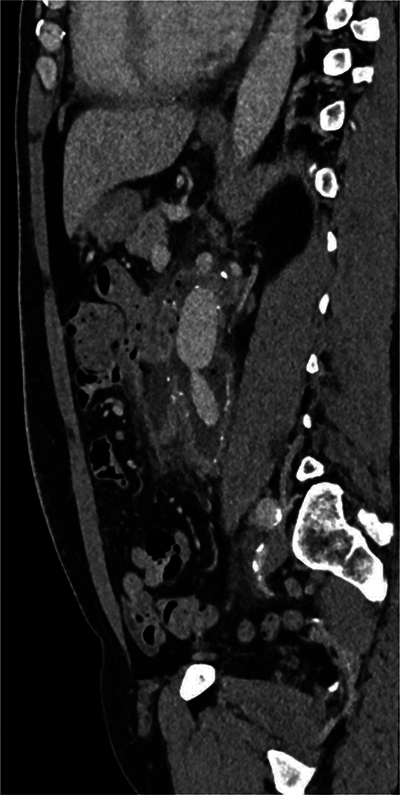

Aortoenteric Fistula with Digestive Contrast Material Leaking in the Aneurysmal Sac.

Teaching point: Aortoenteric fistula, a major complication of aortic surgery, can be identified with certainty on CT scan with opacification of the intestinal tract.